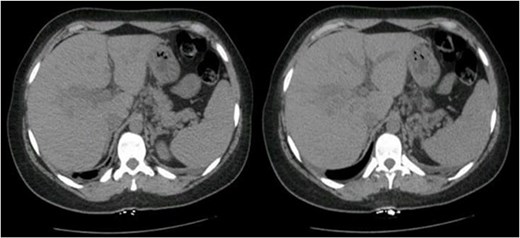

Postoperatively, her liver enzyme level continued to increase. Abdominal and pelvic computed tomography (CT) with IV contrast revealed multiple ill-defined, non-enhancing liver lesions, the largest measuring ~2.7 cm in segment VII, suggestive of hepatic infarction with mild periportal edema (Fig. 1). The liver appeared normal in size and shape with no focal lesions.

Abdominal and pelvic CT with IV contrast showed multiple scattered, ill-defined, and non-enhancing liver lesions, the largest measuring ~2.7 cm in segment VII.